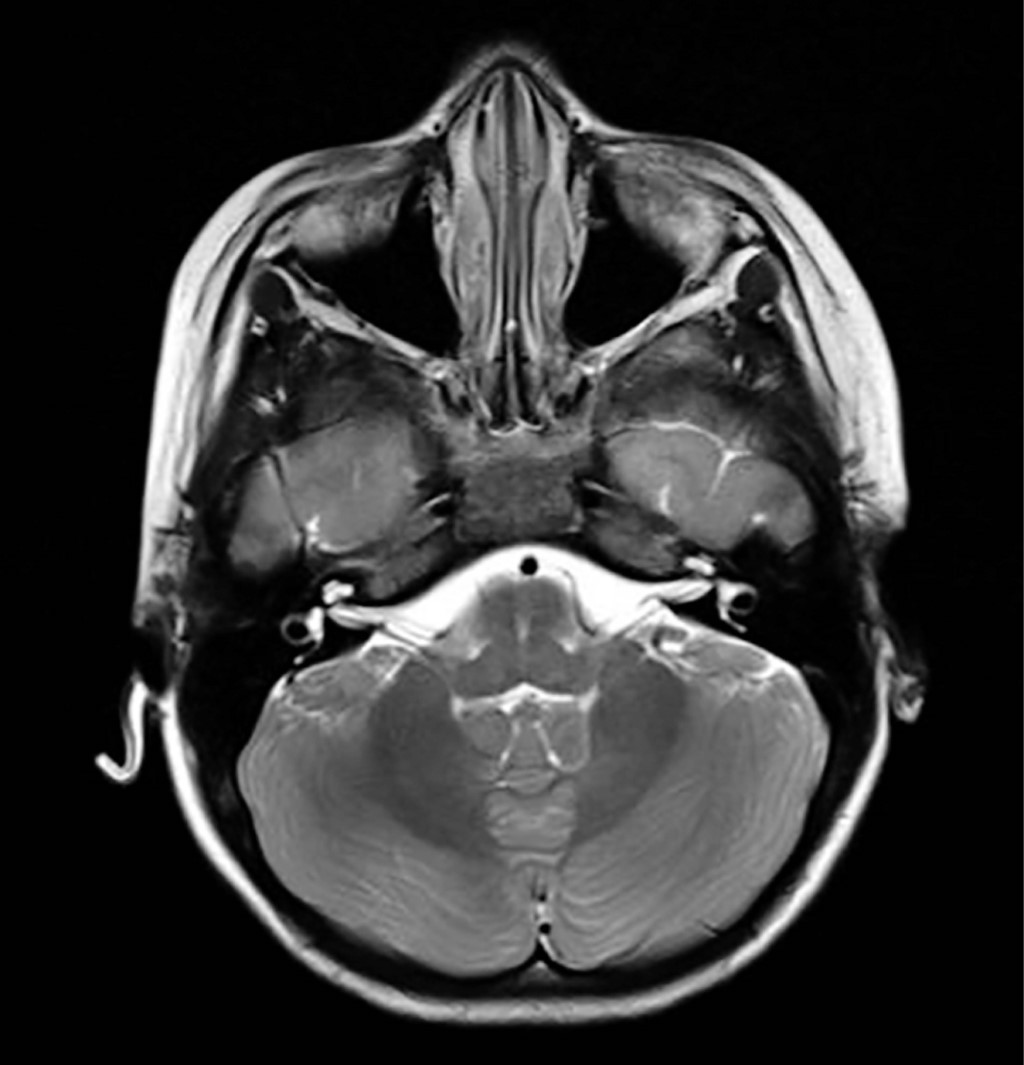

Se trata de paciente femenino de cinco años de edad que ingresa al Servicio de Urgencias en el Hospital Angeles México con signos vitales en parámetros normales, presenta mioclonías focalizadas en miembro torácico derecho, emesis, atetosis y relajación de esfínteres. En urgencias presenta nuevamente crisis focalizadas en el miembro torácico derecho. En hospitalización persiste con crisis convulsivas refractarias a tratamiento. Se realizan paraclínicos (hemocultivo y hemograma) y se recaba electroencefalograma (EEG) y resonancia magnética (RM), la cual muestra cambios morfológicos, leucoaraiosis (Figura 1) y alteraciones vasculares (Figura 2). Posteriormente, se realiza punción lumbar con presencia de anticuerpos anti-NMDA y tomografía por emisión de positrones y tomografía computarizada que muestra hipometabolismo severo en sistema nervioso central. Ingresa a UTIP para sedoanalgesia, plasmaféresis y aplicación de inmunoglobulina intravenosa e inmunomoduladores.

Figura 1